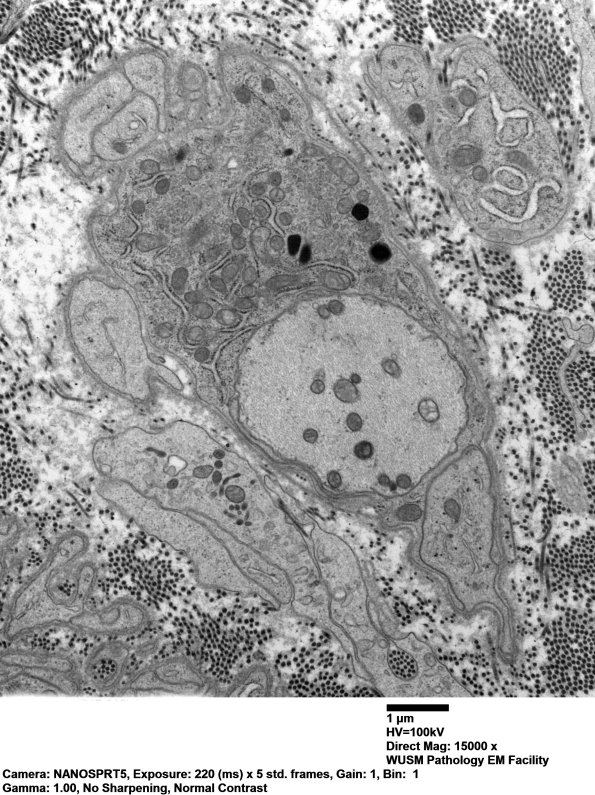

3B6,7 This demyelinated axon is adjacent to a Schwann cell with collections of organelles including prominent rough endoplasmic reticulum (RER). (electron micrographs)